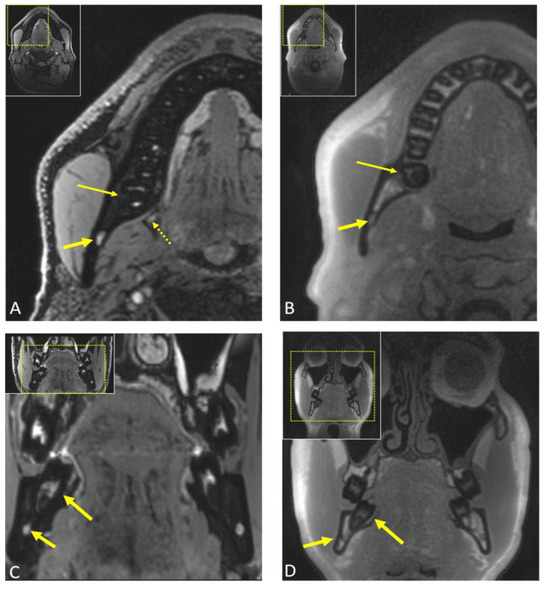

2.5. Magnetic Resonance Imaging (MRI)

- Miloro, M.; Halkias, L.E.; Slone, H.W.; Chakeres, D.W. Assessment of the lingual nerve in the third molar region using magnetic resonance imaging. J. Oral Maxillofac. Surg. 1997, 55, 134–137. [Google Scholar] [CrossRef] [PubMed]

- Al-Haj Husain, A.; Solomons, M.; Stadlinger, B.; Pejicic, R.; Winklhofer, S.; Piccirelli, M.; Valdec, S. Visualization of the Inferior Alveolar Nerve and Lingual Nerve Using MRI in Oral and Maxillofacial Surgery: A Systematic Review. Diagnostics 2021, 11, 1657. [Google Scholar] [CrossRef] [PubMed]

- Al-Haj Husain, A.; Stadlinger, B.; Winklhofer, S.; Müller, M.; Piccirelli, M.; Valdec, S. Mandibular Third Molar Surgery: Intraosseous Localization of the Inferior Alveolar Nerve Using 3D Double-Echo Steady-State MRI (3D-DESS). Diagnostics 2021, 11, 1245. [Google Scholar] [CrossRef] [PubMed]

- Fujii, H.; Fujita, A.; Yang, A.; Kanazawa, H.; Buch, K.; Sakai, O.; Sugimoto, H. Visualization of the Peripheral Branches of the Mandibular Division of the Trigeminal Nerve on 3D Double-Echo Steady-State with Water Excitation Sequence. AJNR Am. J. Neuroradiol. 2015, 36, 1333–1337. [Google Scholar] [CrossRef]

- Al-Haj Husain, A.; Valdec, S.; Stadlinger, B.; Rucker, M.; Piccirelli, M.; Winklhofer, S. Preoperative visualization of the lingual nerve by 3D double-echo steady-state MRI in surgical third molar extraction treatment. Clin. Oral Investig. 2022, 26, 2043–2053. [Google Scholar] [CrossRef]

- Valdec, S.; Al-Haj Husain, A.; Winklhofer, S.; Müller, M.; Piccirelli, M.; Stadlinger, B. Comparison of Preoperative Cone-Beam Computed Tomography and 3D-Double Echo Steady-State MRI in Third Molar Surgery. J. Clin. Med. 2021, 10, 4768. [Google Scholar] [CrossRef]

- Burian, E.; Probst, F.A.; Weidlich, D.; Cornelius, C.P.; Maier, L.; Robl, T.; Zimmer, C.; Karampinos, D.C.; Ritschl, L.M.; Probst, M. MRI of the inferior alveolar nerve and lingual nerve-anatomical variation and morphometric benchmark values of nerve diameters in healthy subjects. Clin. Oral Investig. 2020, 24, 2625–2634. [Google Scholar] [CrossRef] [PubMed]